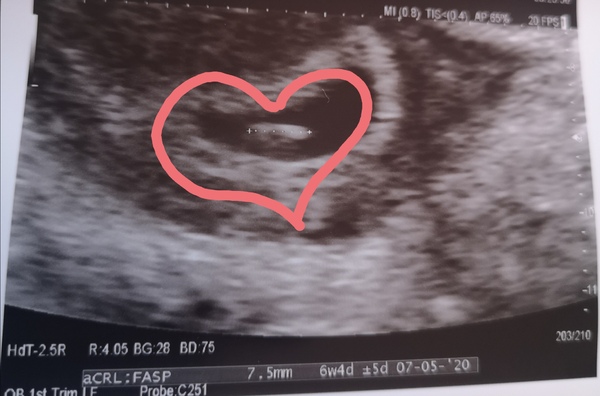

Hi ladies! I had my early scan yesterday morning and all is well. I thought i was about 7 weeks but they have moved it back a few days. Was so lovely to see the wee blobs heartbeat ❤️ I just want to tell everyone but I'll just leave it to in here.